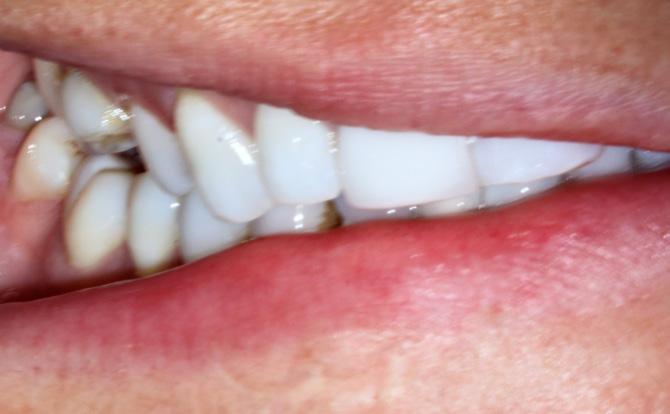

Oral examination revealed several shallow ulcers with erythematous borders affecting the buccal mucosa and the lateral borders of the tongue (Fig. 1). The patient reported significant discomfort while eating and speaking. Blood investigations were unremarkable. He was prescribed dexamethasone mouthwash and Difflam rinse, but there was no improvement. Methotrexate-induced oral ulceration was suspected. The patient’s rheumatologist was contacted, and methotrexate was temporarily withheld. Supportive therapy

with a topical corticosteroid mouth rinse was continued. Within two weeks, the ulcers healed completely (Fig 2). Methotrexate was later resumed at the same dose with continued 5 mg folic acid daily, and no recurrence was noted at follow-up.

Case 1

Fig. 1

Multiple painful ulcers on the buccal mucosa and lateral border of the tongue in a patient taking low-dose methotrexate.

Fig. 2

Complete resolution of ulcers within 2 weeks.

Case 2

Fig. 2 A

Multiple painful ulcers on the tongue and buccal mucosa in an 80-year-old female taking methotrexate and folic acid, resistant to initial topical therapy and antifungal treatment.

2 B

Marked improvement and healing noticed after discontinuing methotrexate for 3 weeks.

Fig.